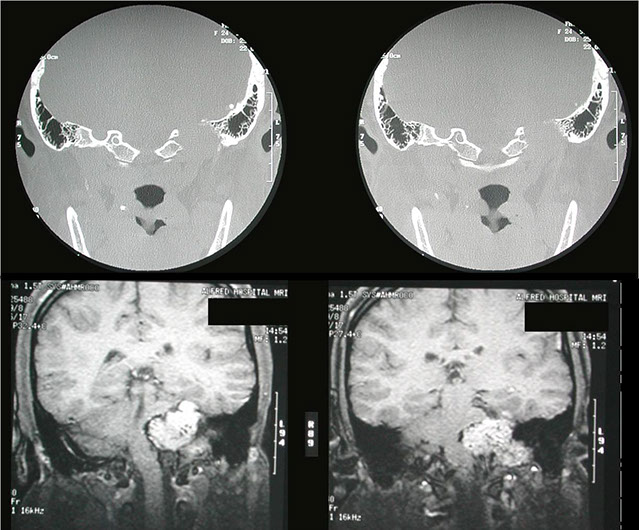

The CT scan shows the bone destructive lesion in the left petrous temporal bone in a patient with headache and ringing in the left ear.

A highly vascular lesion consistent with a glomus tumour was seen as the cause of the bony defect on the MR scan.

Angiography demonstrates a very vascular mass fed by the ascending pharyngeal artery as they often are.

During the embolisation procedure it was noted that the patient did not converse with the radiologist and a cerebrovascular accident was suspected, here confirmed by a filling defect in the left middle cerebral artery.

Immediate thrombolysis removed the blood clot and restored patient consciousness.